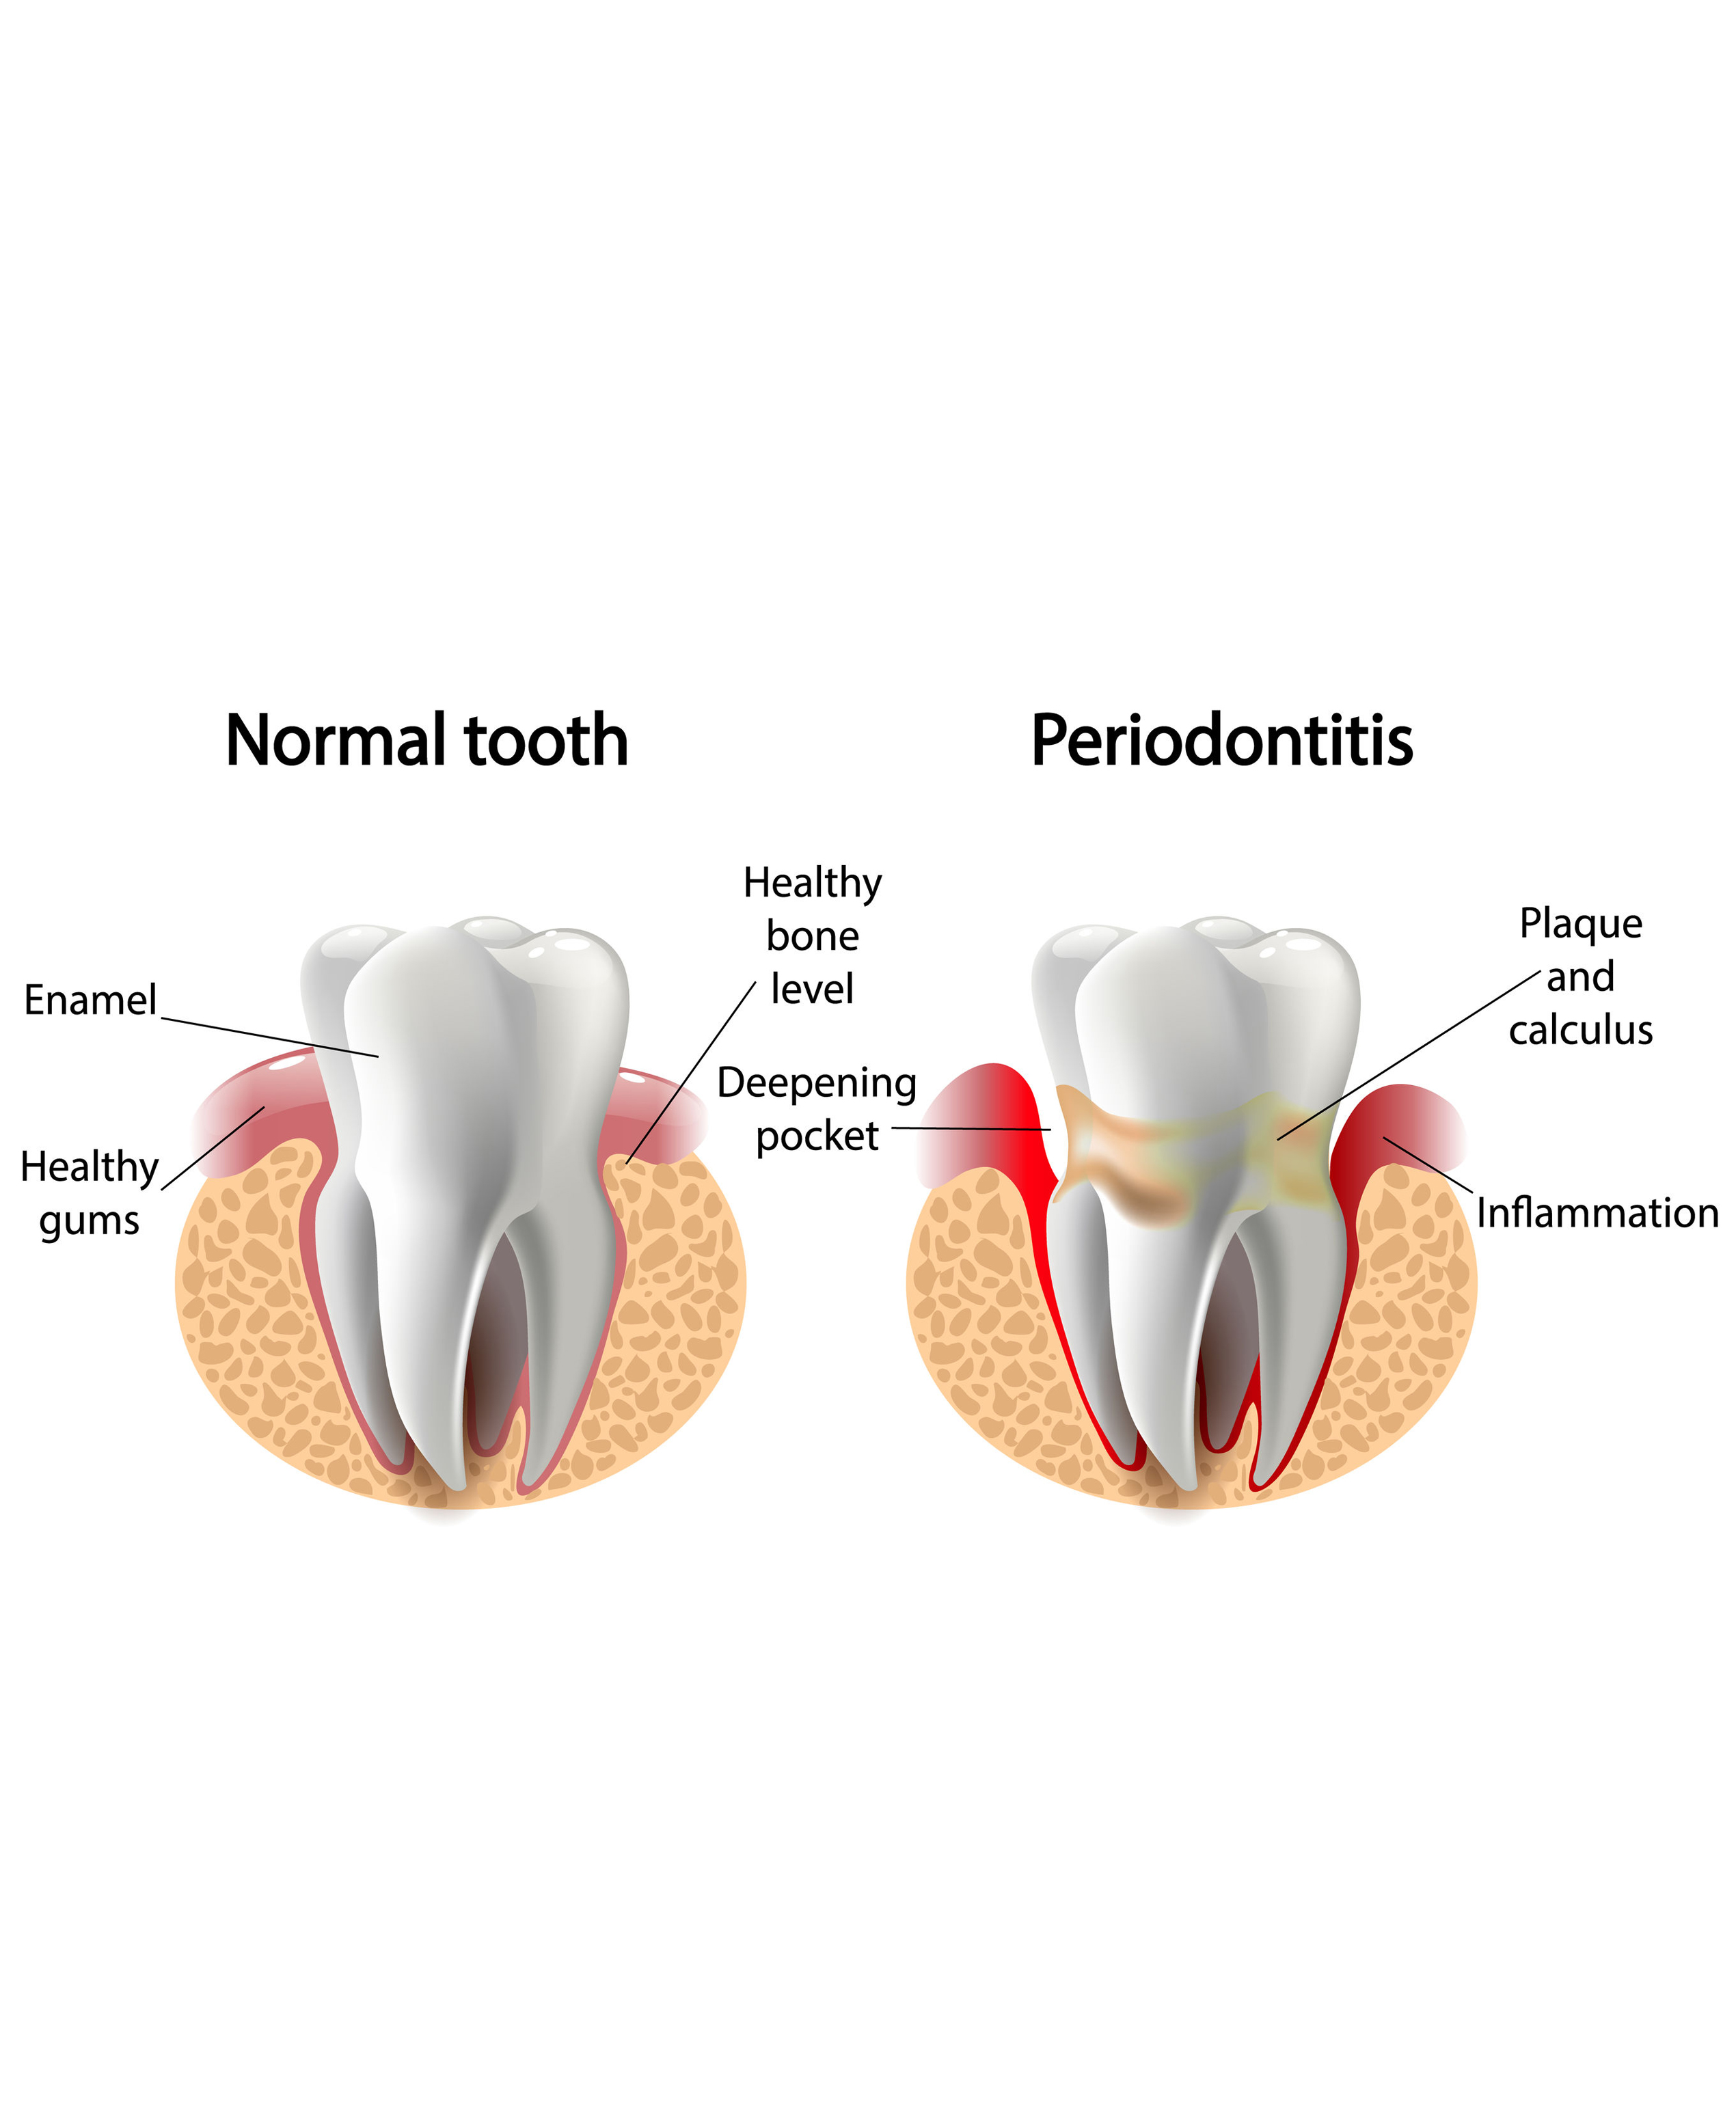

Although serious gum infections aren’t extremely common, they can lead to major issues if not treated in a timely manner. While most of us want to keep our teeth and gums healthy, your gums can be prone to gum infection if not cared for properly. Identifying warning signs that can lead to infected gums is an important way to help prevent further gum disease and all the side effects that come with it.

This advanced gum infection treatment cleans deeply between your gums and teeth—all the way to the roots.

If your gum disease is severe, flap surgery may be necessary involving bone or tissue grafts.